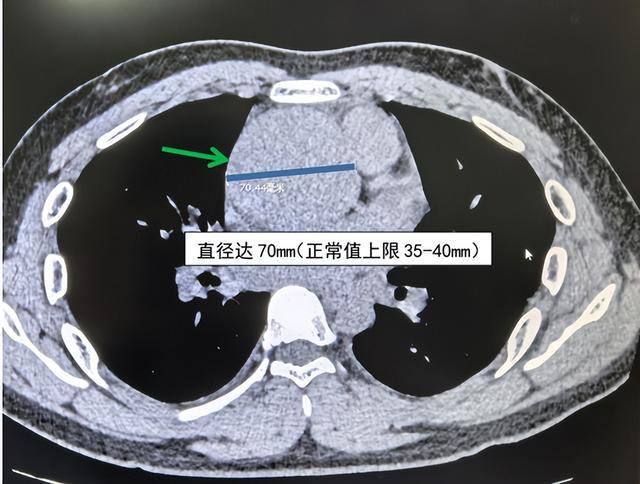

魏骥荣在审阅CT时,发现一个极其危险的信号:患者升主动脉特别推广,直径达70mm,而升主动脉直径平素值上限为35-40mm,高度怀疑是主动脉夹层!魏骥荣连忙脱手危境值复核经由,在上司医师汤薇薇的引导下,团队连忙锁定该恶果为“危境值”。

(箭头所指处为主动脉夹层处)